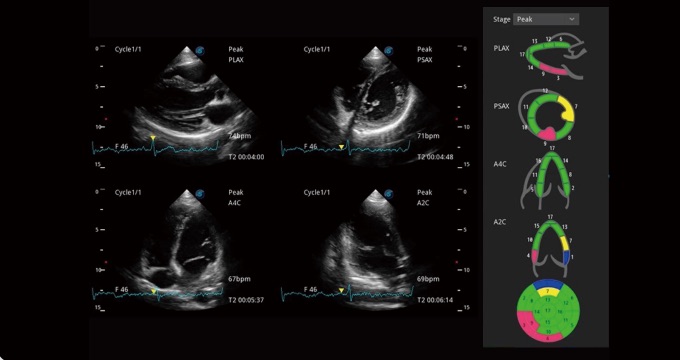

支持运动和药物负荷协议、多心动周期存储选择,为临床观察心肌负荷状态下的室壁节段运动、评估心肌缺血状态提供更多的解决方案。

通过心肌识别技术和二维斑点追踪技术相结合,计算心肌各节段的应变应变率、速度、位移并以曲线图显示,实现整体或者局部心肌定量分析。同时可呈现牛眼图直观和准确诊断心肌的运动情况。